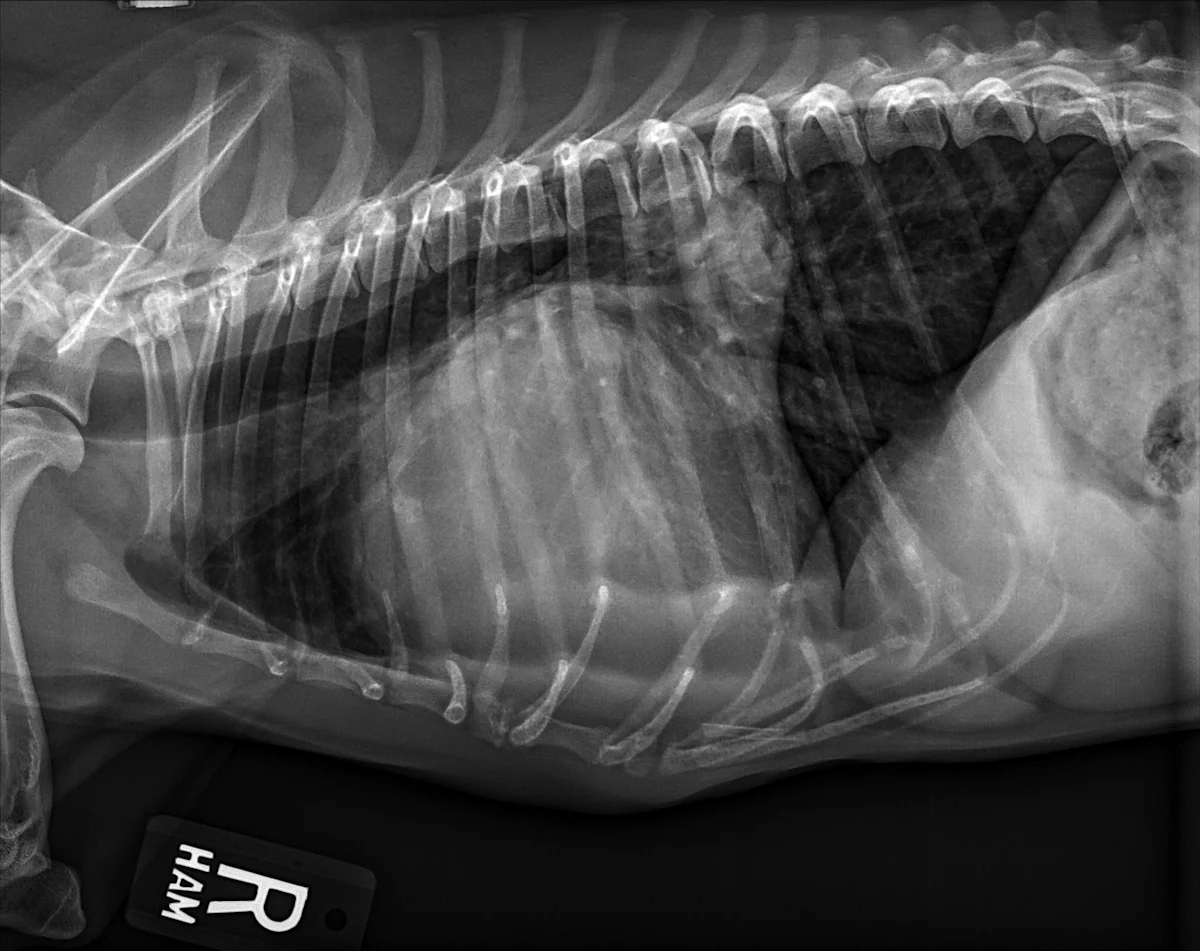

At least 2 orthogonal views, ideally taken during peak inspiration, are necessary for appropriate radiographic study of the cardiovascular system; however, a 3-view study is ideal for comprehensive evaluation of the thorax. Some differences should be considered when deciding to acquire a right versus left lateral projection and a dorsoventral (DV) versus ventrodorsal (VD) projection. On the left lateral view, the cardiac silhouette is typically more rounded and the apex is further elevated from the sternum than in the right lateral view (Figure 1). In the DV view, the cardiac silhouette is commonly displaced cranially and to the left by the diaphragm and appears more rounded than in the VD view. The caudal pulmonary vasculature is better delineated in the DV view, whereas the lung field (particularly the accessory lobe) is better evaluated in the VD view (Figure 2).

FIGURE 2 Normal DV (left) and VD (right) projections of the thorax in a large, crossbreed dog. The cardiac silhouette appears more rounded, and the caudal pulmonary vasculature is more apparent (arrowheads) in the DV view compared with the VD view. In some DV projections, the cardiac silhouette can appear significantly displaced to the left (not apparent in this case). Images courtesy of Federico Villaplana Grosso, DACVR, DECVR